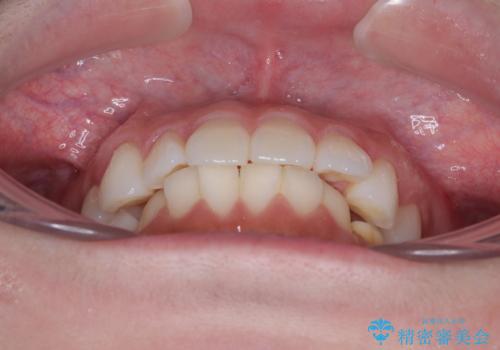

- 上下前歯の叢生を気にして来院された患者様です。

軽度な叢生であり、安価で短期間の治療を規模されていたため、インビザライン・モデレートを用いて矯正治療を行うこととしました。